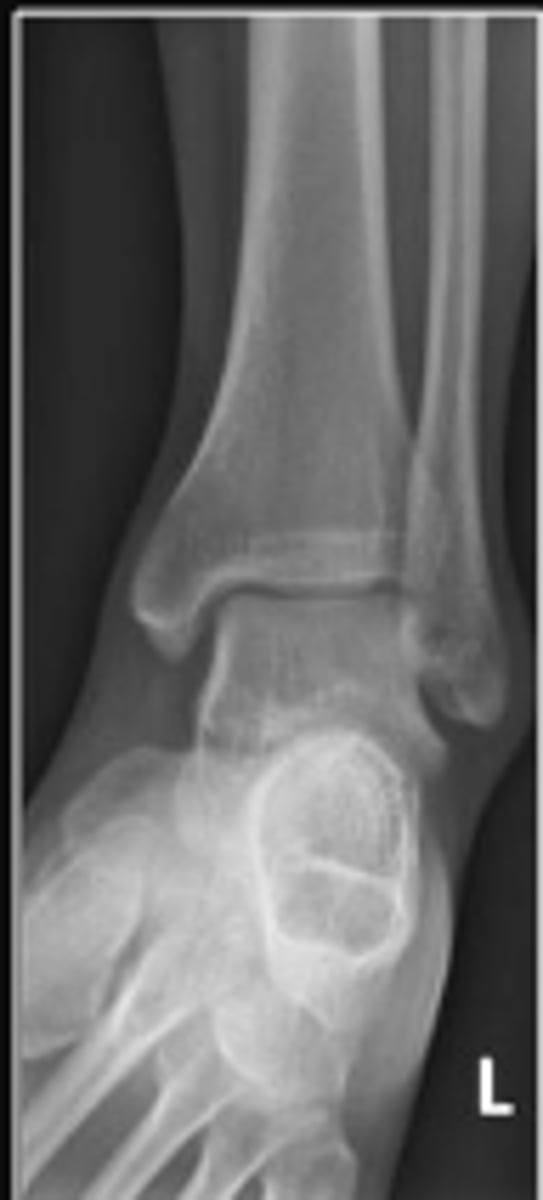

Left AP ankle

What is the name of the radiographic view?